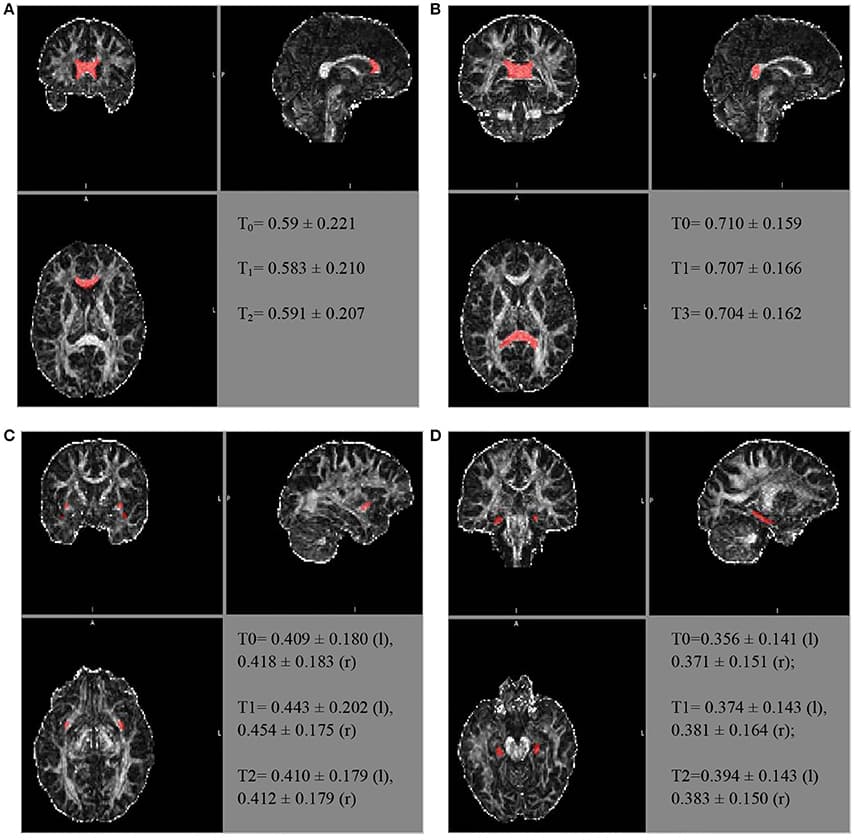

Similarly, further mean FA estimates were performed for the hippocampal cingulate fascicule and the splenium of the CC, bilateral, using the JHU-ICBM-labels-1 mm. The FA estimates were also performed for the bilateral uncinate fascicule from the WM atlas JHU-ICBM-tracts-prob-1 mm, which has better fascicule representation, following the steps described above. Figure 2 presents similar FA values for the different ROIs during the follow-up. The mean FA values of the CC's splenium was 0.710 ± 0.159 before treatment, 0.707 ± 0.166 for T1, and 0.704 ± 0.162 for T2. The mean FA values for the hippocampal cingulate fascicule for T0, T1, and T2 were: 0.356 ± 0.141 (l:left) 0.371 ± 0.151 (r:right); 0.374 ± 0.143 (l), 0.381 ± 0.164 (r); and 0.394 ± 0.143 (l) 0.383 ± 0.150 (r), respectively. For the uncinate fascicule, the results of mean FA values for T0, T1, and T2 were: 0.409 ± 0.180 (l), 0.418 ± 0.183 (r); 0.443 ± 0.202 (l), 0.454 ± 0.175 (r); and 0.410 ± 0.179 (l), 0.412±0.179 (r), respectively.

FIGURE 2. The longitudinal FA variation for different regions of interest. The atlas showing the locations for the (A) genu of the CC, (B) splenium of the CC, (C) uncinate fascicule right r/l, and (D) cingulate hippocampal fascicule r/l.

The FA of the genu of the CC, using the JHU tract probe in MATLAB, presented small variations between T0, T1, and T2 (T0 = 0.523473; T1 = 0.507267; T3 = 0.491564), toward FA reduction. After adjusting by the JHU tract probe FSL, the analyses were similar among the periods of assessment (T0 = 0.504 ± 0.216; T1 = 0.493 ± 0.205; T2 = 0.502 ± 0.2066), as well as after the JHU/Labels, 1 mm (T0 = 0.59 ± 0.221; T1 = 0.583 ± 0.210; T2 = 0.591 ± 0.207), without a reduction trend (Figure 2).